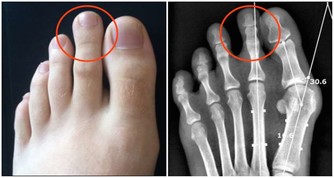

頸椎病患者更適合仰臥,這樣可以順應頸椎的生理彎曲,為達到枕頭支撐頸部的目的,患者最好將蕎麥皮枕頭的形狀稍加整理,使其形成一個中間凹、兩邊凸的形狀,高起的部分相當於自己的拳頭。睡眠時儘量枕著中間凹的部位,開始時不太習慣,經過長期適應,可以最大程度減少睡眠過程中的翻身動作。 蕎麥皮枕頭的適應性強,填充枕頭時,不要填得太滿,否則影響其塑形,填充約70%即可。(蘇玉梅)